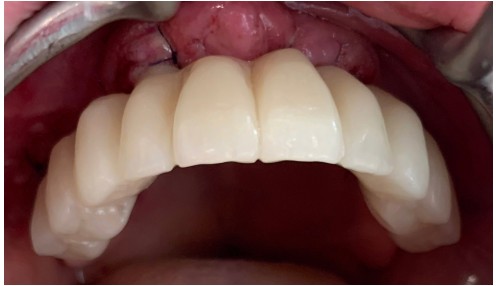

Se colocan 4 implantes Zygoma según planificación 3D guiada bajo sedación IV, Carga inmediata a las 24 horas.

La paciente fue rehabilitada de forma definitiva a los tres de meses en su clínica origen.